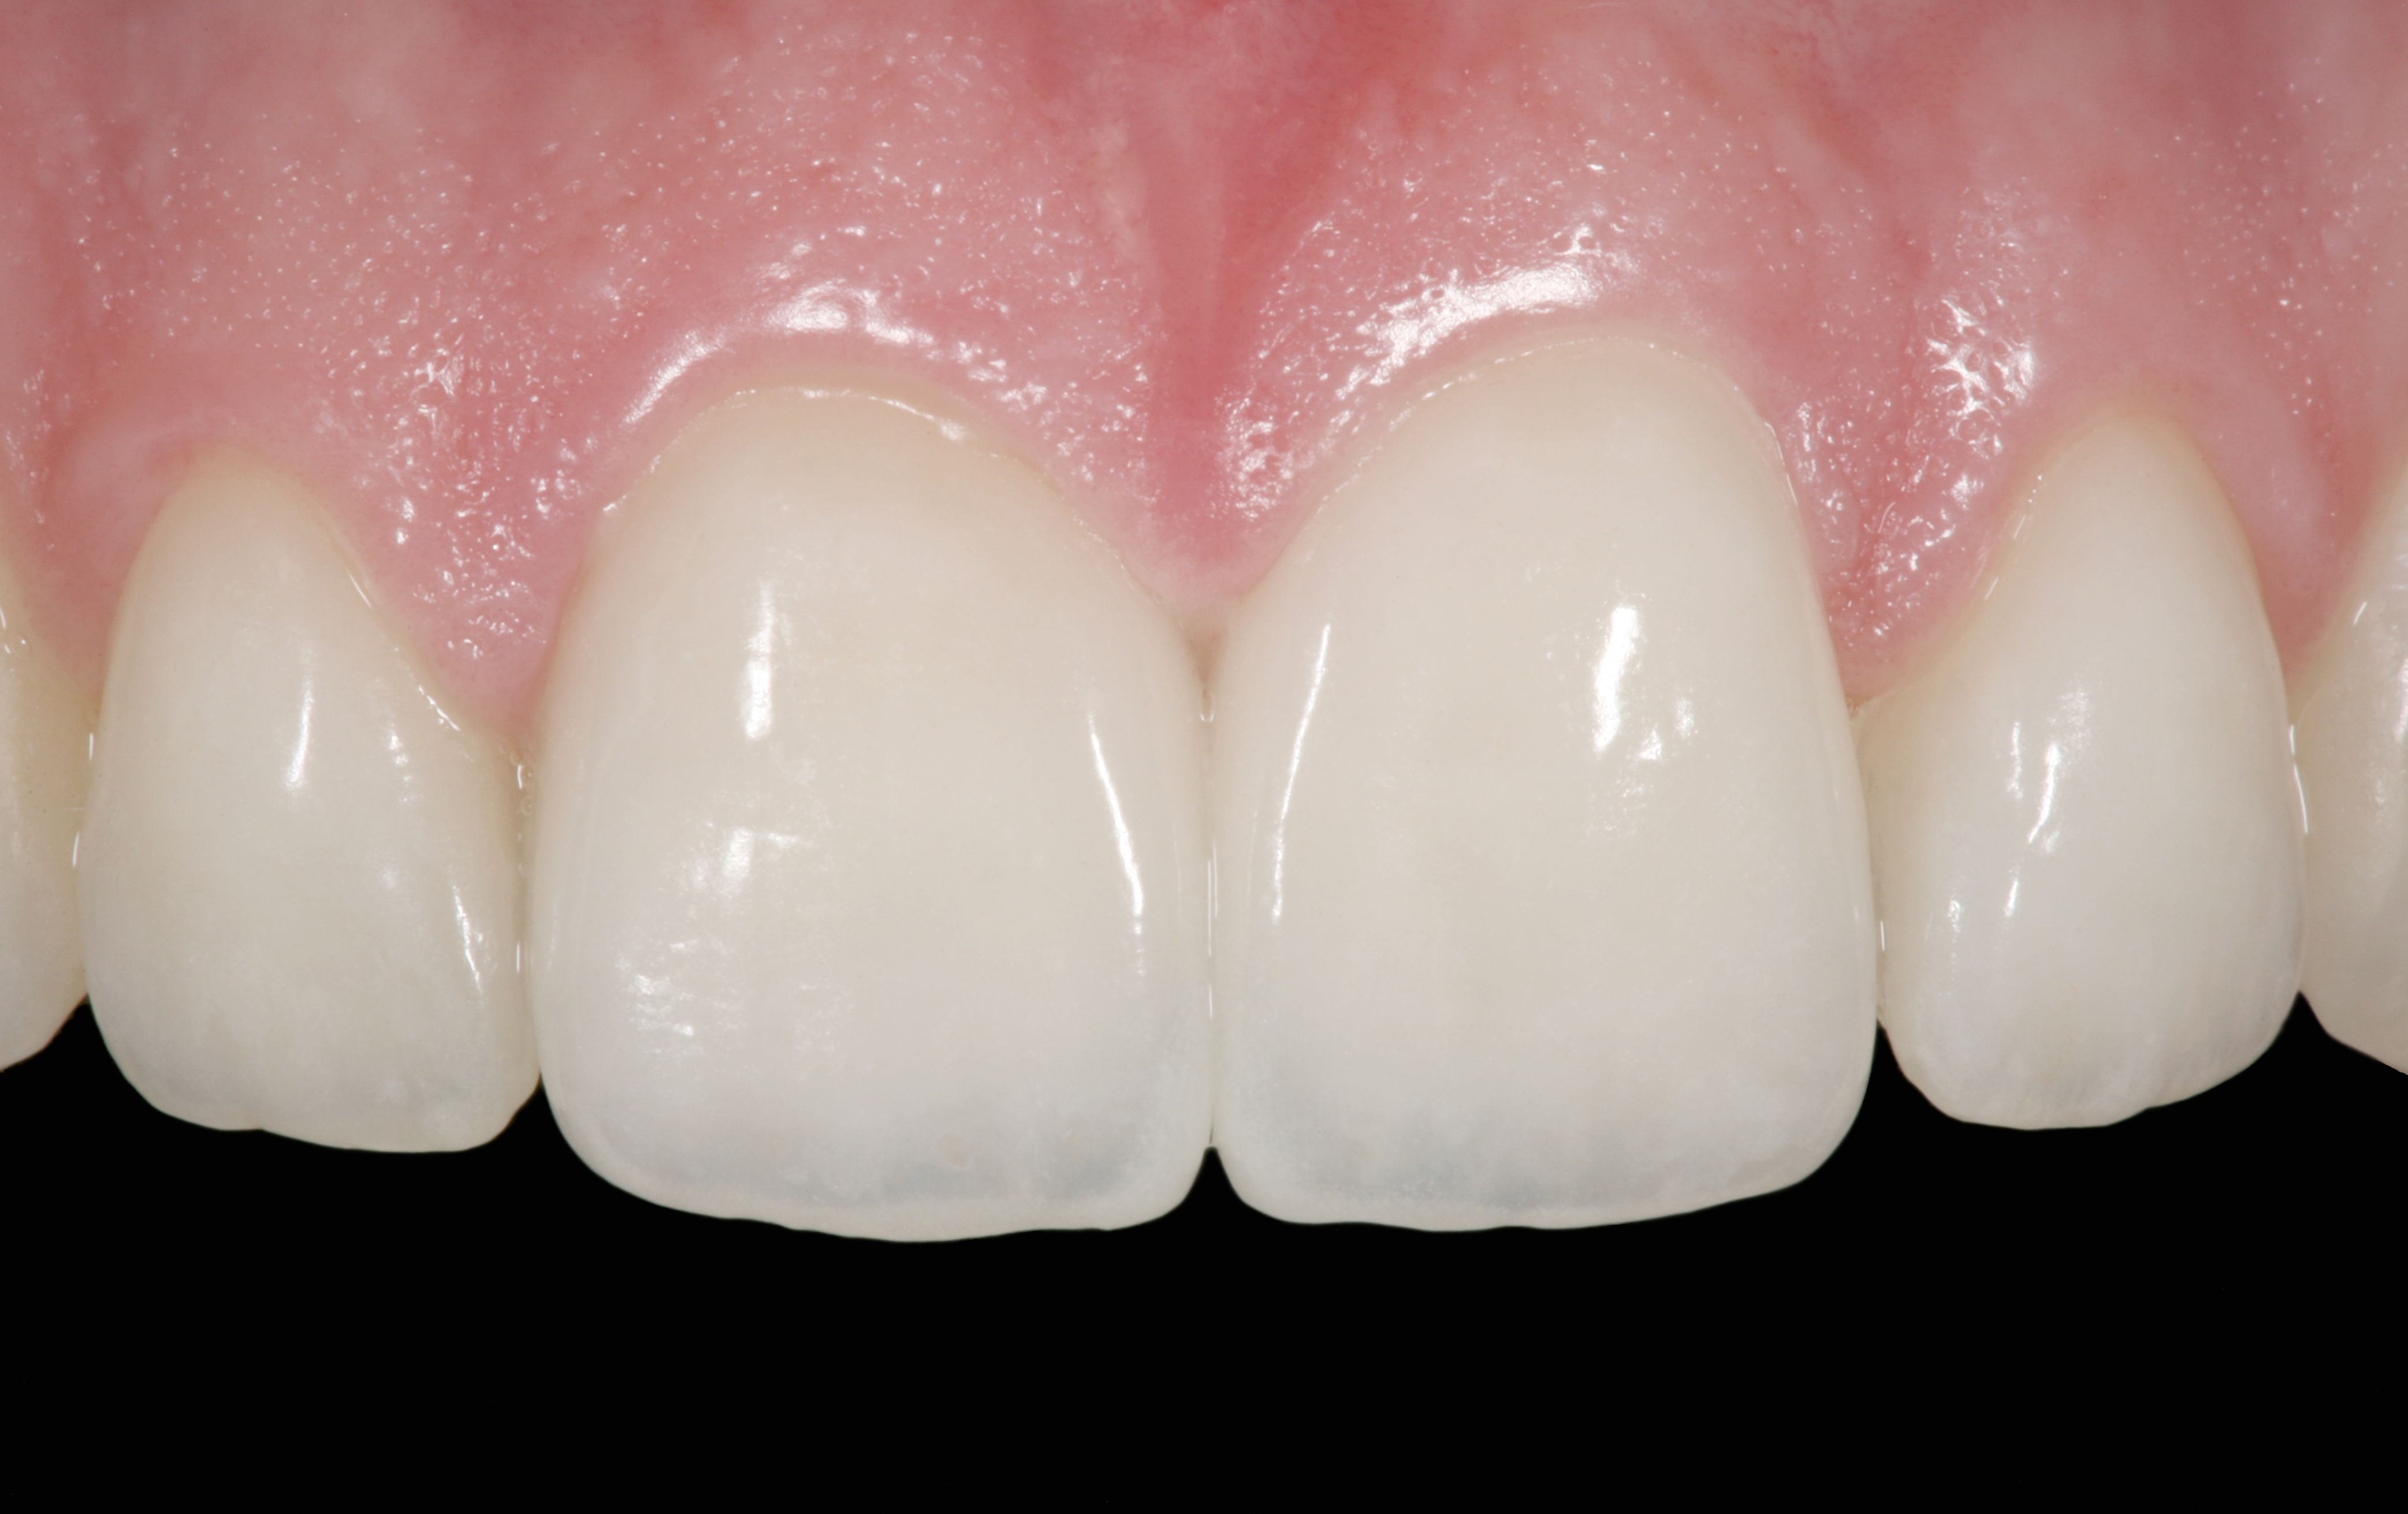

The clinical application of this protocol is illustrated in a patient situation where laminate veneers were placed on four maxillary incisors to replace lost tooth structure and restore function and esthetics. The failing restorations were removed, followed by a conservative veneer preparation (Figure 1 and Figure 2). The bonding surfaces of the feldspathic porcelain veneers were acid-etched with hydrofluoric acid for 2 minutes (Figure 3) and thoroughly rinsed. Then a silane coupling agent was applied (Figure 4). Figure 5 demonstrates the situation after bonding the veneers to the teeth with a composite resin luting agent.

The pretreatment situation.

Figure 1

Figure 13